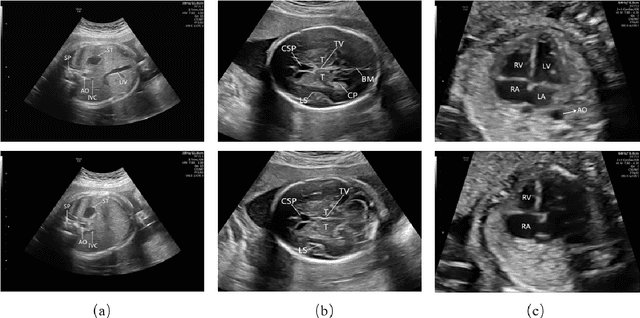

Abstract:The quality control of fetal sonographic (FS) images is essential for the correct biometric measurements and fetal anomaly diagnosis. However, quality control requires professional sonographers to perform and is often labor-intensive. To solve this problem, we propose an automatic image quality assessment scheme based on multi-task learning to assist in FS image quality control. An essential criterion for FS image quality control is that all the essential anatomical structures in the section should appear full and remarkable with a clear boundary. Therefore, our scheme aims to identify those essential anatomical structures to judge whether an FS image is the standard image, which is achieved by three convolutional neural networks. The Feature Extraction Network aims to extract deep level features of FS images. Based on the extracted features, the Class Prediction Network determines whether the structure meets the standard and Region Proposal Network identifies its position. The scheme has been applied to three types of fetal sections, which are the head, abdominal, and heart. The experimental results show that our method can make a quality assessment of an FS image within less a second. Also, our method achieves competitive performance in both the detection and classification compared with state-of-the-art methods.